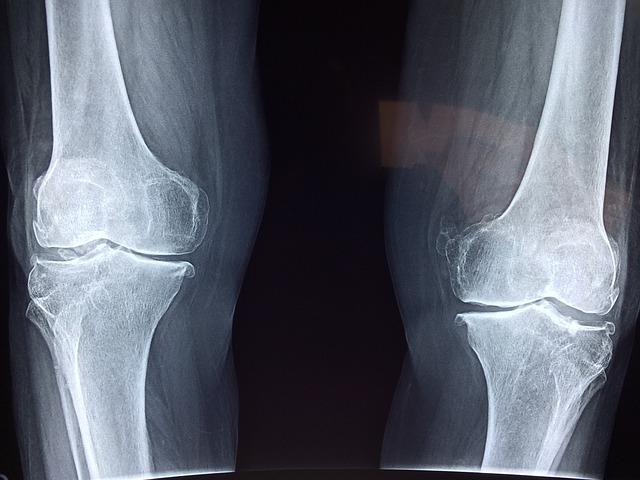

Now,youcanavoid expensiveknee replacementsurgery andtameyourchronic oracutepain. Recentstudiesshowthatstem celltherapy,canrebuild damagedtissueandprovide significantimprovementfor patientsdiagnosedwithan orthopedicdisorder.

Newdatasuggeststhatstemcelltherapymayevenreduce kneepainbyasmuchas75%whencombinedwithother healing dlii h h i lh